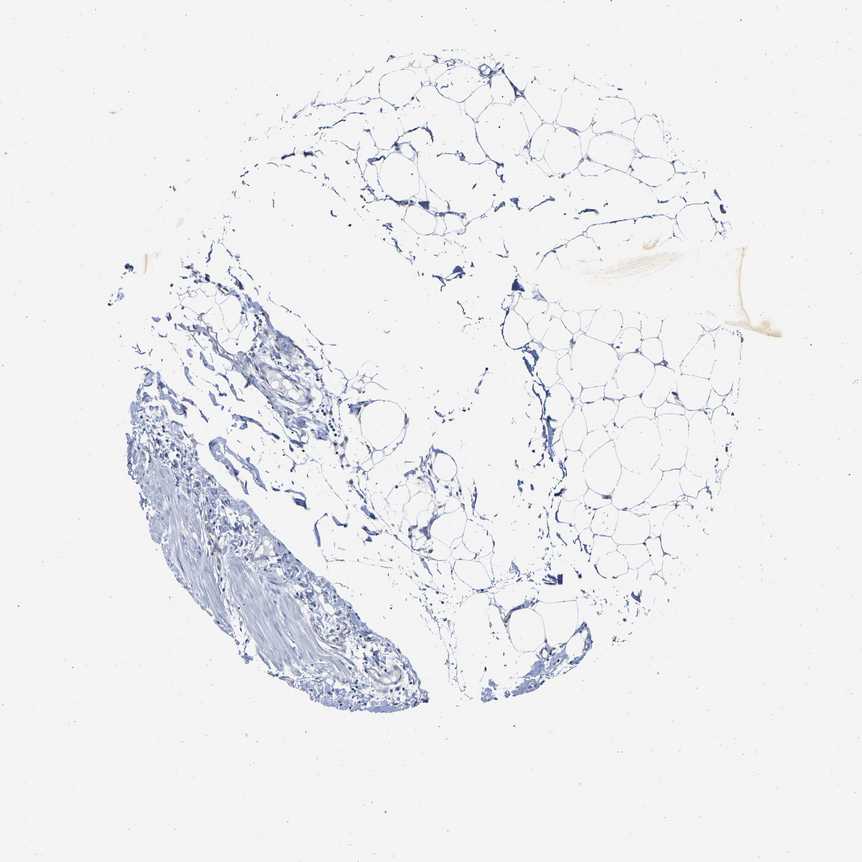

ADIPOSE TISSUE - Antibody stainingi

Antibody staining in the annotated cell types in the current human tissue is reported as not detected, low, medium, or high, based on conventional immunohistochemistry profiling in selected tissues. This score is based on the combination of the staining intensity and fraction of stained cells.

Each image is clickable and will lead to virtual microscopy that enables deeper exploration of all samples and also displays staining intensity scores, fraction scores and subcellular localization as well as patient and tissue information for each sample.

Antibody HPA019049Antibody HPA019051

Adipocytes Not detectedNot detected